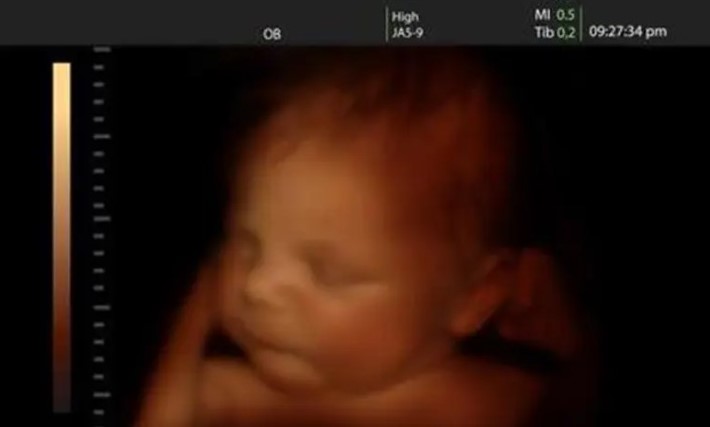

Οι επιστήμονες μίλησαν: 4 παράγοντες που επηρεάζουν την ευφυΐα του εμβρύου

Κατηγορίες: Κοινωνιολογικά (κοινωνική πρόνοια & οικογενειακά θέματα), Υγεία και ιατρικά θέματα

Όλο και περισσότερες γυναίκες τα τελευταία χρόνια αποφασίζουν να κάνουν παιδιά σε μεγαλύτερη ηλικία. Κάτι που, από πολλούς, κρίνεται αρνητικά....